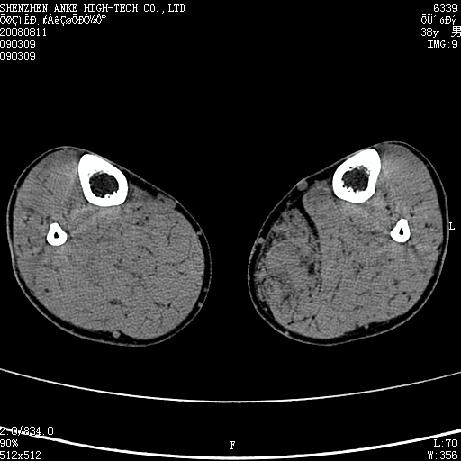

患者,男,38岁,右小腿疼痛性包块1月,查体:右小腿可扪及约5x4cm大小包块,压痛.

左小腿内侧软组织病变,性质待定(血管瘤?);建议行mri检查。